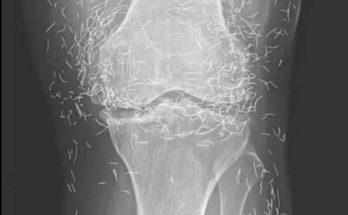

When a 65-year-old woman in South Korea went to the doctor because of worsening knee pain, no one expected the scans to reveal anything unusual. The visit was supposed to …